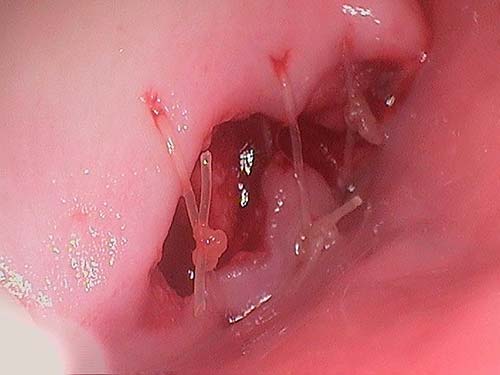

Tooth extraction is the process of surgically removing a tooth from a patient’s tooth socket. The process is completed within our dental clinic by our qualified dental surgeon.

Before your surgery, our dentist will discuss the process for the extraction with the you. They may ask you to take pain relief or antibiotic medication before the procedure to prepare your gums for the extraction process. Depending on the size, shape and location of the specific tooth, you may return to your day-to-day activities immediately or require a few days of rest to ensure proper healing. In the majority of situations we will be able to quite accurately gauge the healing process before the tooth is extracted.

While wisdom tooth extraction is an extremely common procedure that takes place on a daily basis across Canada, there are small risks for patients to consider. All patients are always given a detailed set of post-operative instructions both verbally and in written form. Following these instructions is paramount to ensuring a smooth healing process. As each case is unique, it’s important to speak with an oral health professional about specific surgical risks before undergoing tooth extraction.

The aftercare process for a wisdom tooth extraction involves avoiding smoking, hot food or drinks, drinking through a straw, vigorous rinsing or spitting. Patients may also use ice-packs and pain-relieving medication to minimize swelling and soreness in their gums, mouth, and cheeks. As each case is unique, our team will tailor your post-operative instructions for your specific case.